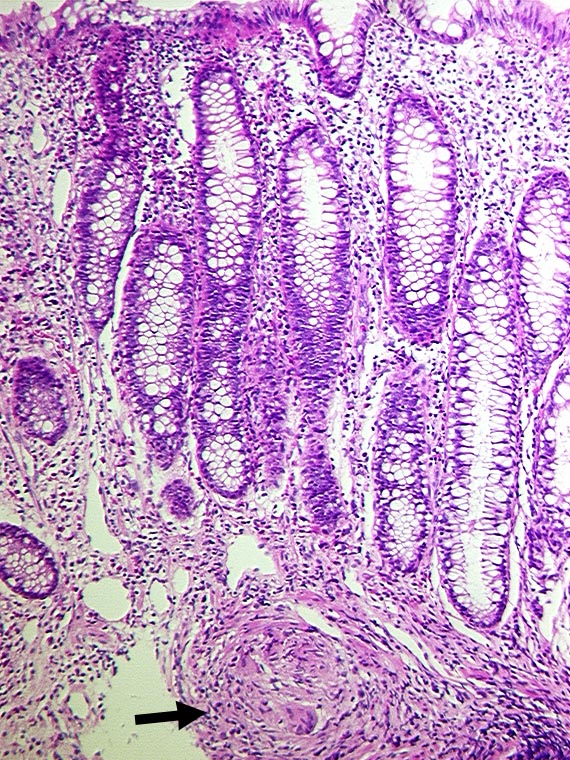

Granulom in der Submukosa bei Morbus Crohn

An dieser Stelle weitgehend unauffällige Mukosa. In der Submukosa ein epitheloidzelliges Granulom mit einer Riesenzelle.

Fokal aktive Entzündung.

Bekannter Morbus Crohn seit 8 Jahren.